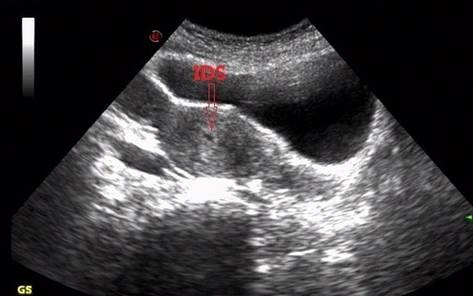

一、蜕膜内征:intradecidual sign

一,蜕膜内征intradecidual sign

增大的子宫内膜呈不对称肥厚并回声增强。用阴道超声扫查,可见宫腔线一侧较厚的内膜内,有一圆形增强回声区,中央有小囊状液性暗区,宫腔线局部突起变形称蜕膜内征。停经29天的早期妊娠囊直径1~2mm。